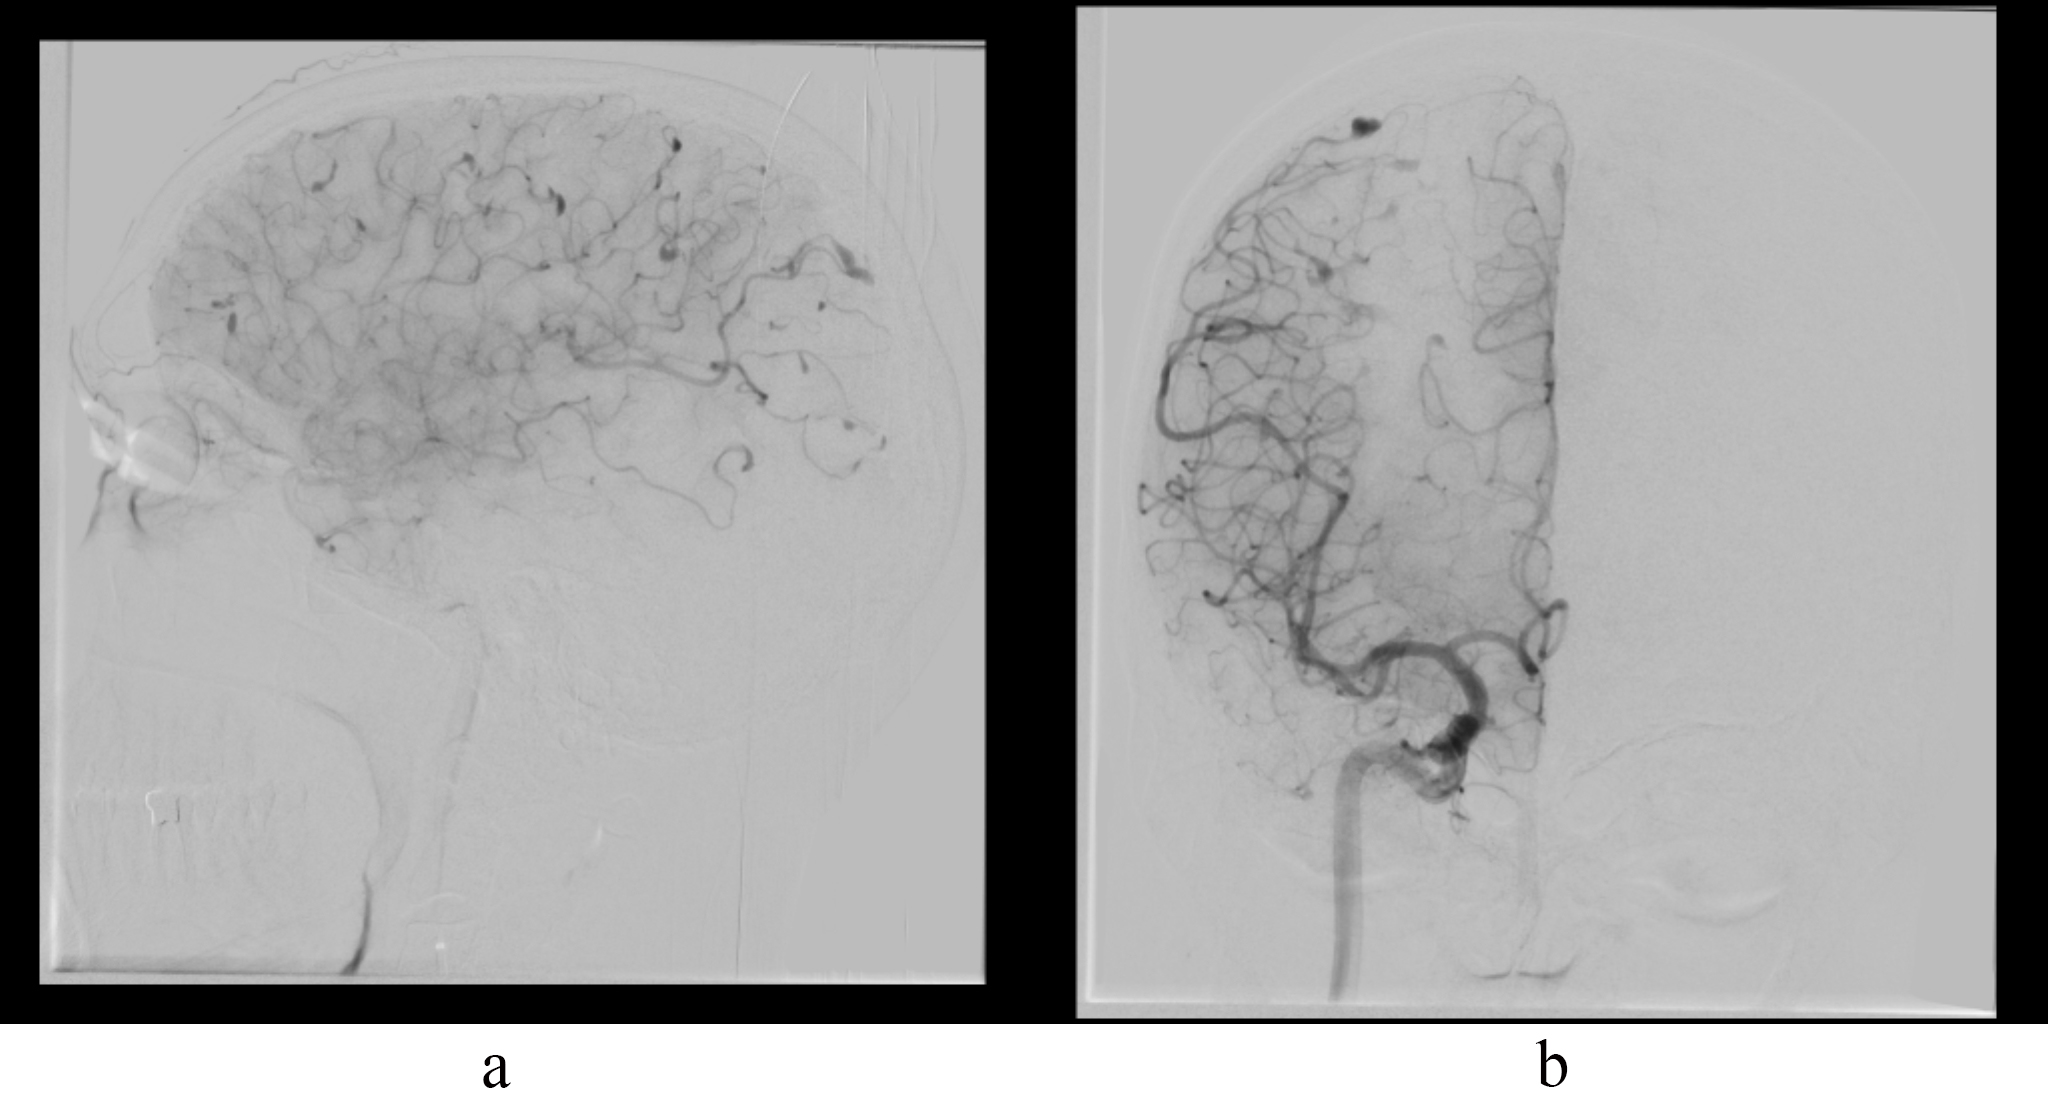

We encountered a 42-year-old male, with a history of total excision of a left atrial myxoma in April 2023, presented in September 2024 with mild weakness, tingling, and numbness in the left upper and lower limbs for two months. He also experienced persistent headaches and had two episodes of generalized tonic-clonic seizures. An echocardiogram confirmed no recurrence of the atrial myxoma. Brain magnetic resonance imaging (MRI) revealed T2/fluid attenuated inversion recovery sequences (FLAIR) heterogeneous mixed-signal intensity lesions in the bilateral parietal, right temporal-occipital, and right frontal regions, accompanied by surrounding edema and heterogeneous post-contrast enhancement, suggestive of parenchymal metastasis (Fig. 1). Digital subtraction angiography (DSA) of the brain demonstrated multiple fusiform aneurysms in the cortical branches of the bilateral anterior cerebral artery (ACA), middle cerebral artery (MCA), and posterior cerebral artery (PCA) (Fig. 2). The treatment options were discussed with him, and he opted to undergo chemotherapy and radiotherapy.

Fig. 2. Multiple fusiform aneurysms on DSA. (a) DSA lateral view shows multiple fusiform aneurysms in ACA and MCA cortical branches. (b) DSA AP view shows multiple fusiform aneurysms in ACA and MCA cortical branches. DSA, digital subtraction angiography; ACA, anterior cerebral artery; MCA, middle cerebral artery; AP, antero-posterior view.